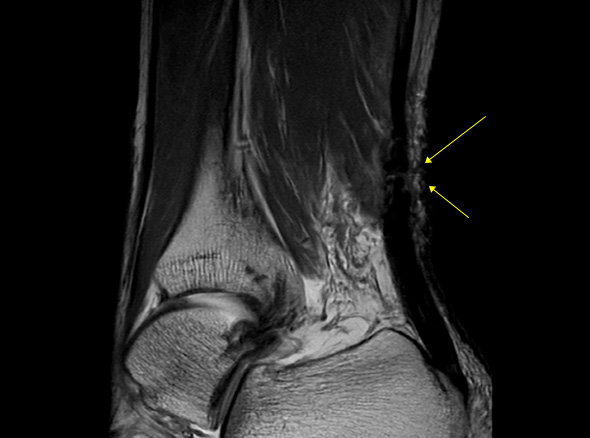

발뒤꿈치 뼈와 종아리 근육을 연결하는 아킬레스건이 부분적으로 또는 완전히 찢어지는 손상입니다.

아킬레스건은 우리 몸에서 가장 크고 강력한 힘줄 중 하나로, 걷기, 뛰기, 점프 등의 동작을 수행하는 데 중요한 역할을 합니다.

* 환자에게 받은 소중한 자료입니다.